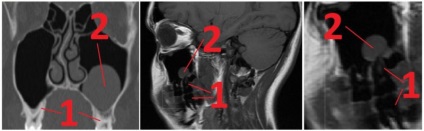

Határozza meg a mértékét pneumatizáció, pontos lokalizációját a gyulladás lehetővé radiográfiás vizsgálatok.

A röntgenfelvételek gyulladt területeken pneumatikus üregek vannak szürkítve